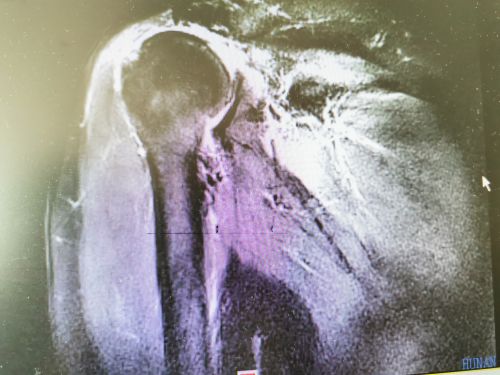

术前核磁共振检查显示,冈上肌全层撕裂伴肌肉回缩。

入院后完善了核磁共振等检查,结果显示:右肩袖损伤(冈上肌腱、冈下肌腱全层撕裂伴回缩)。“对于这种巨大的、不可修复的肩袖撕裂,普通的修补手术效果不好,只能进行反肩关节置换”,王靖主任医师带领团队经过认真仔细的分析讨论,为患者制定精准的手术方案后,于2019年5月26日在全麻下为余女士施行右侧反肩关节置换手术。通过这种省内首次开展的新术式,让患者肩关节旋转中心下移,术后,患者可以利用三角肌的力量完成肩袖外展的功能,恢复正常的关节活动度。